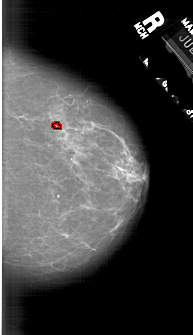

A_1740_1.LEFT_MLO

LEFT_MLO LINES 6136 PIXELS_PER_LINE 3466 BITS_PER_PIXEL 12 RESOLUTION 43.5 OVERLAY

FILE: A_1740_1.LEFT_MLO.OVERLAY

TOTAL_ABNORMALITIES 1

ABNORMALITY 1

LESION_TYPE CALCIFICATION TYPE PLEOMORPHIC DISTRIBUTION CLUSTERED

ASSESSMENT 4

SUBTLETY 5

PATHOLOGY BENIGN_WITHOUT_CALLBACK

TOTAL_OUTLINES 1

BOUNDARY